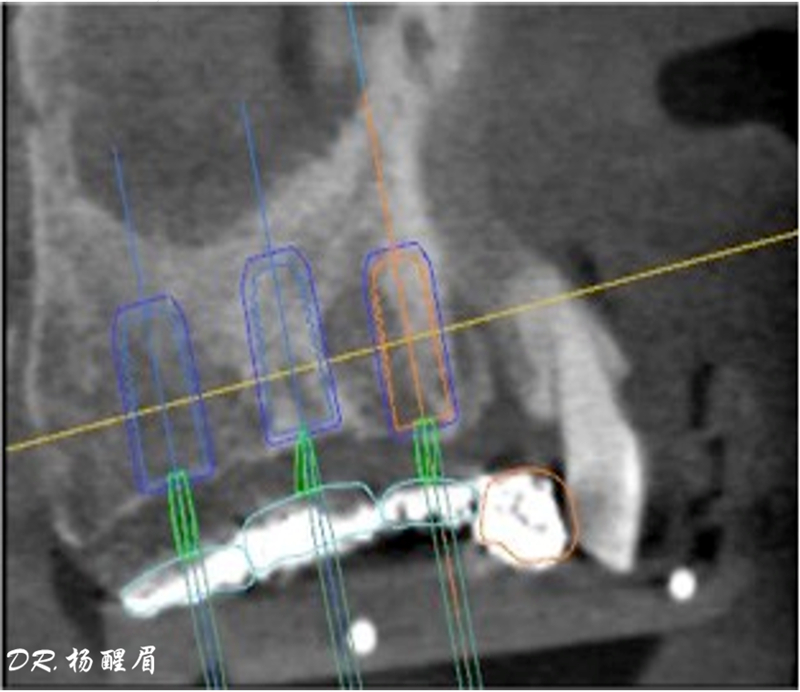

®根據(jù)CBCT中牙冠顯影位置,按照修復引導種植的原則進行方案設計

®使用迪凱爾易植美導航軟件進行方案設計,確定種植體使用方案,以及種植位點,方向和深度

®多顆植體種植方案應盡量保持軸向在同水平線上